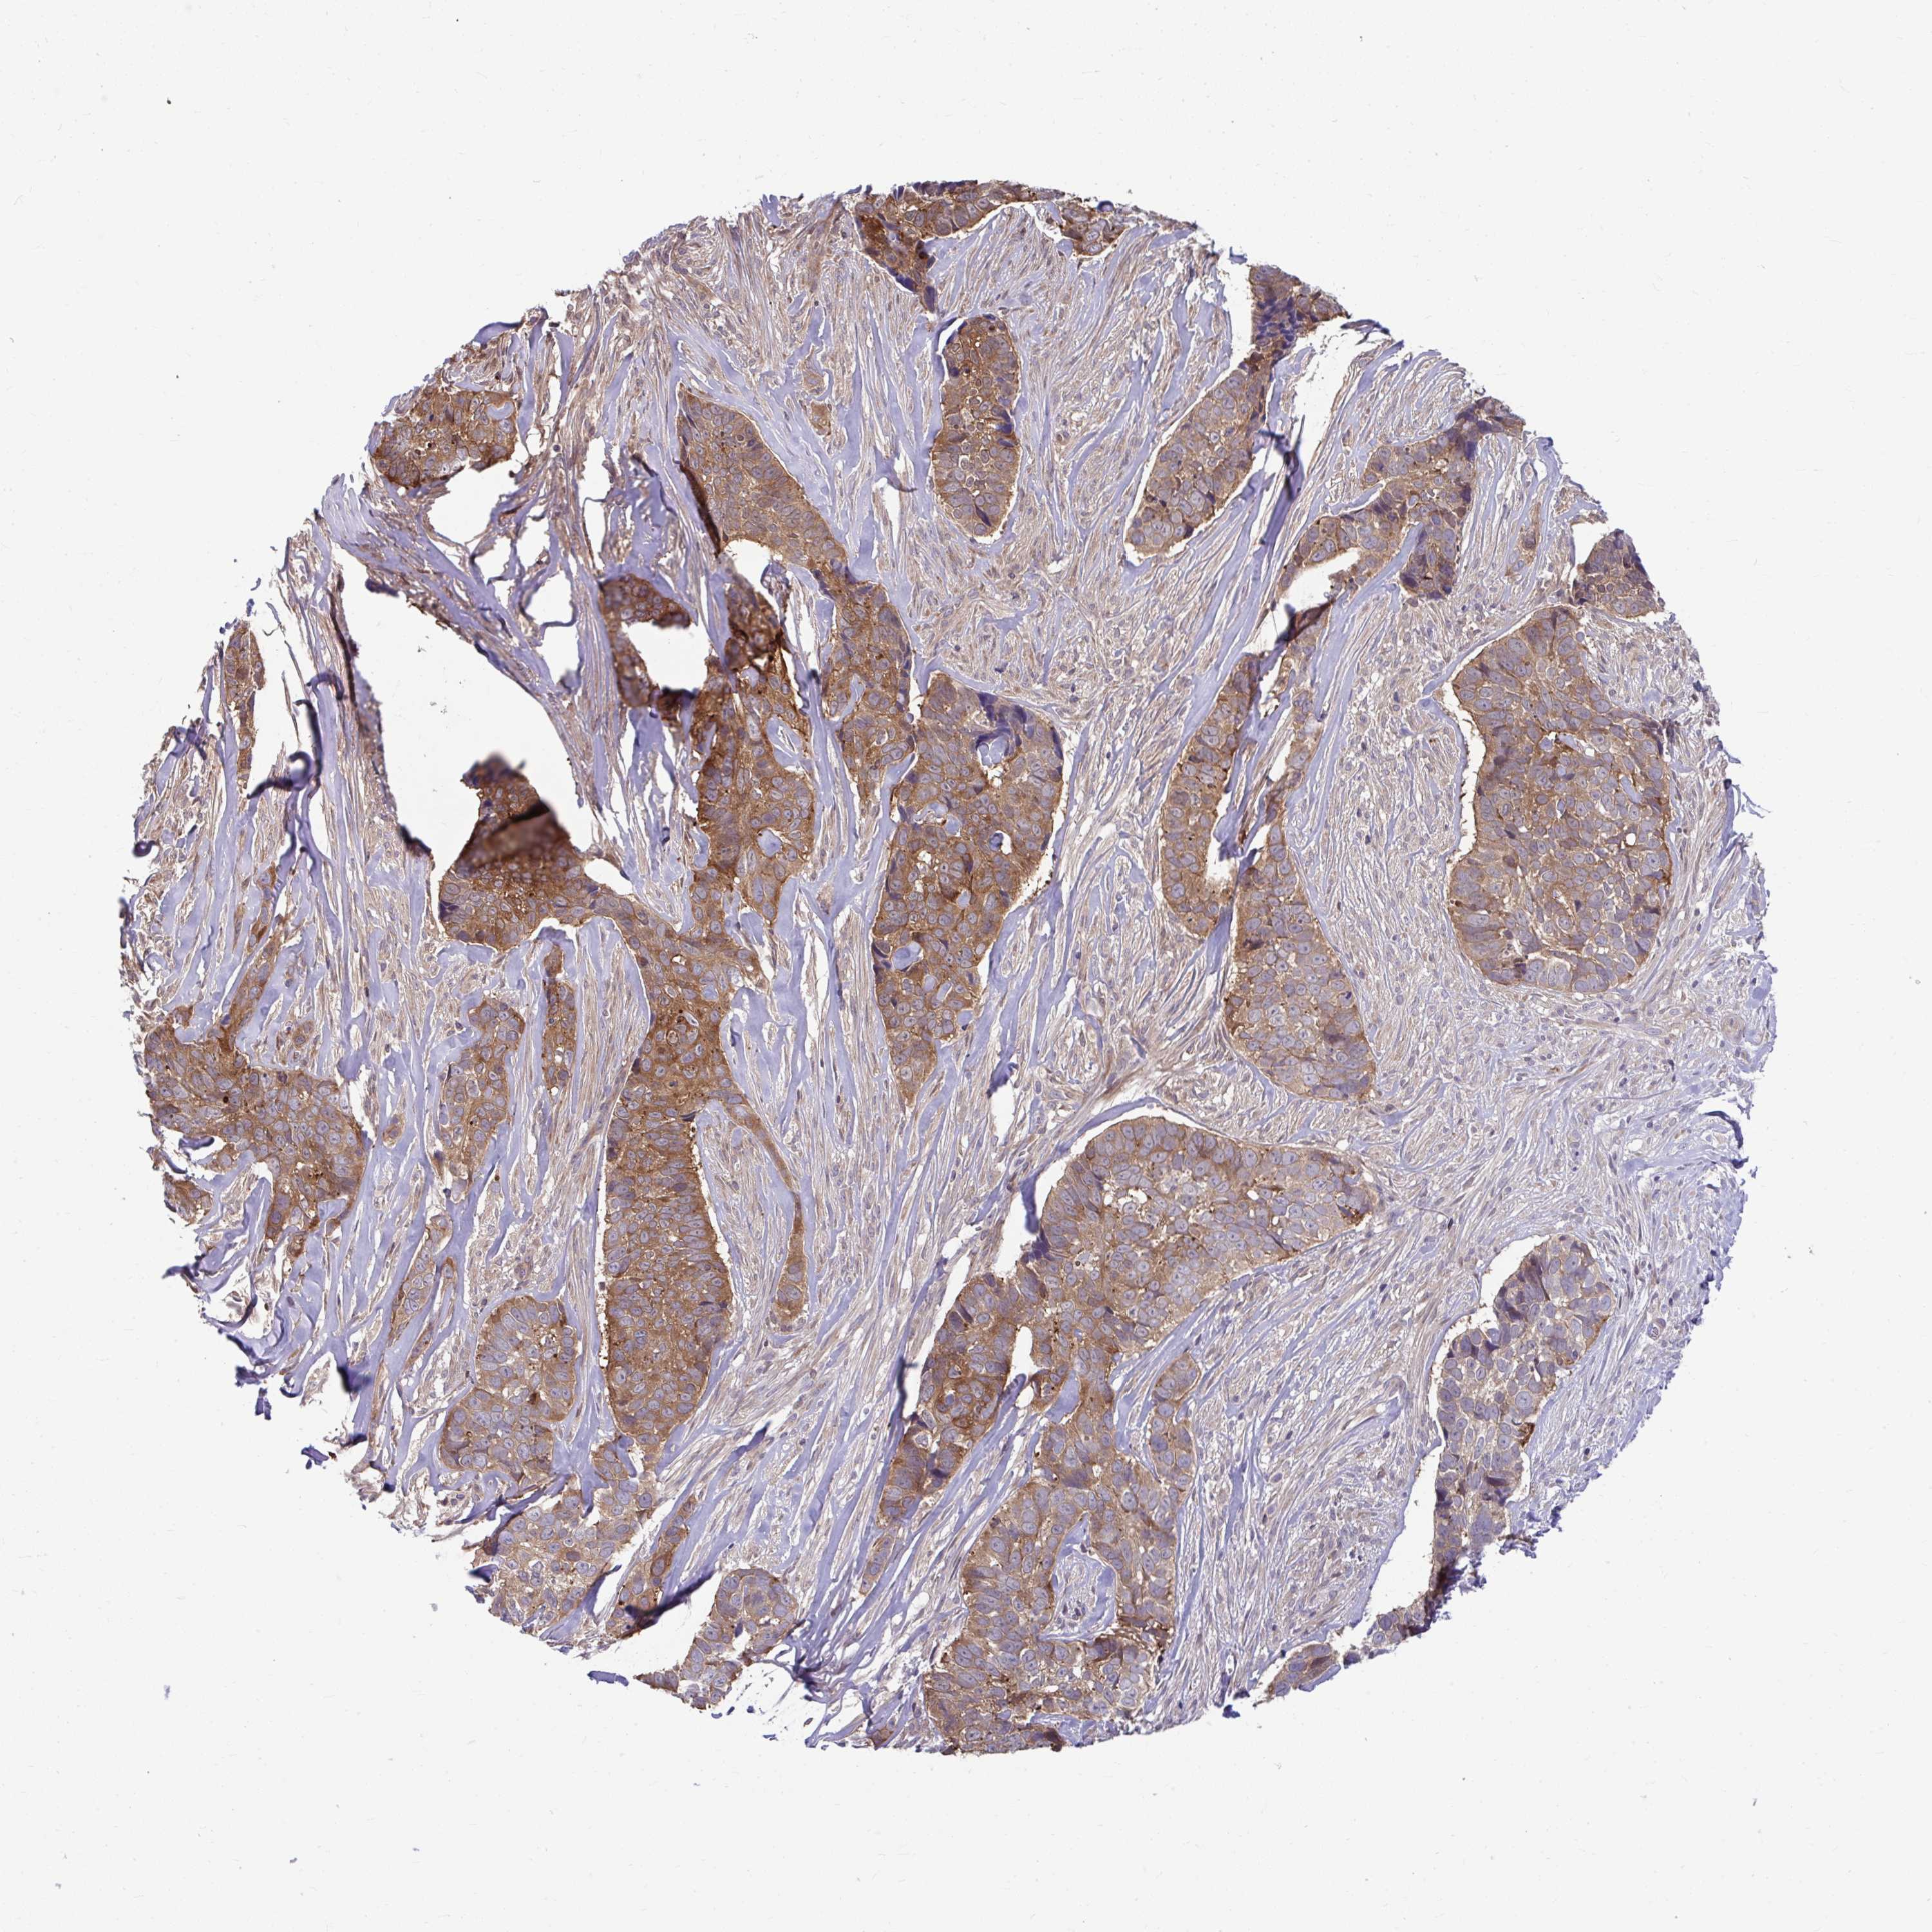

SKIN CANCER - Protein expressioni

A mouse-over function shows sample information and annotation data. Click on an image to view it in a full screen mode. Samples can be filtered based on level of antibody staining by selecting one or several of the following categories: high, medium, low and not detected. The assay and annotation is described here.

Antibody stainingi

Antibody staining in the annotated cell types in the current human tissue is reported as not detected, low, medium, or high, based on conventional immunohistochemistry profiling in selected tissues. This score is based on the combination of the staining intensity and fraction of stained cells.

Each image is clickable and will lead to virtual microscopy that enables deeper exploration of all samples and also displays staining intensity scores, fraction scores and subcellular localization as well as patient and tissue information for each sample.

Antibody HPA059271

Staining

High

Medium

Low

Not detected

Intensity

Strong

Moderate

Weak

Negative

Quantity

>75%

75%-25%

<25%

None

Location

Nuclear

Cytoplasmic/membranous

Cytoplasmic/membranous,nuclear

Basal cell carcinoma

Squamous cell carcinoma, NOS